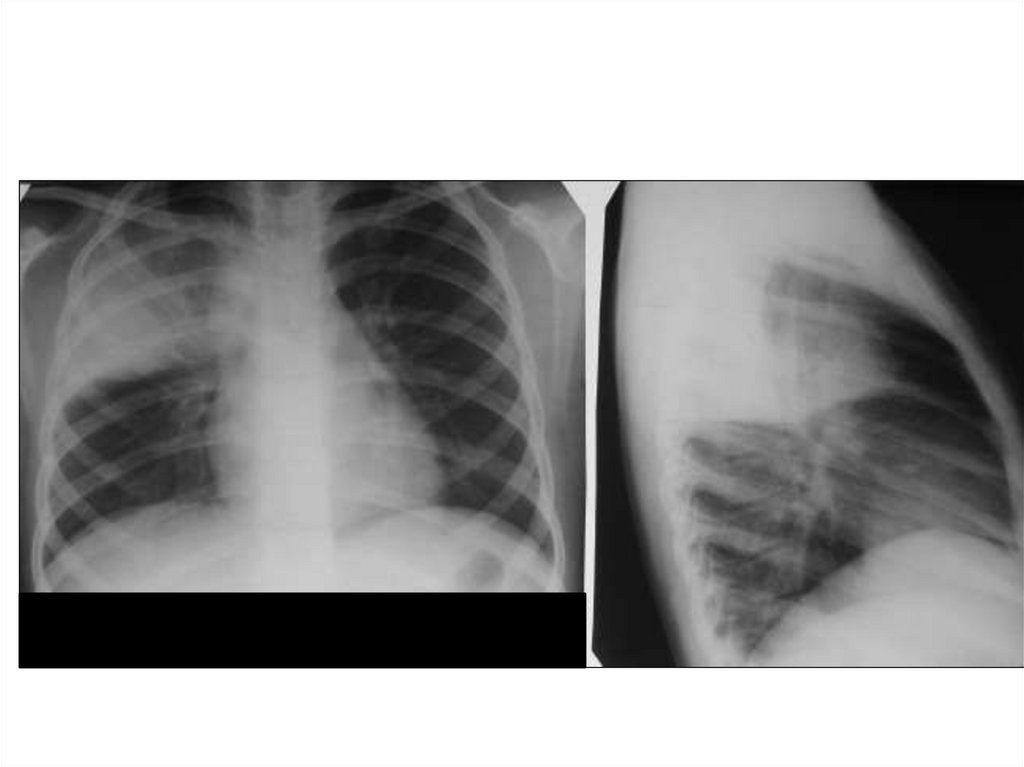

Ателектаз